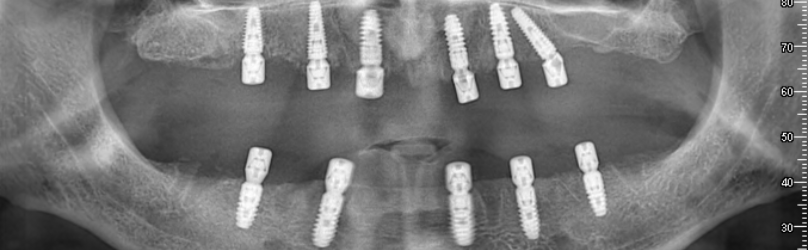

Dans les étapes ultérieures, vous pouvez regarder des vidéos sur la façon de placer des implants et de produire des prothèses. Ces vidéos visent à fournir une perspective informative à nos patients en montrant chaque étape du processus. Chaque étape est réalisée minutieusement par nos médecins experts.